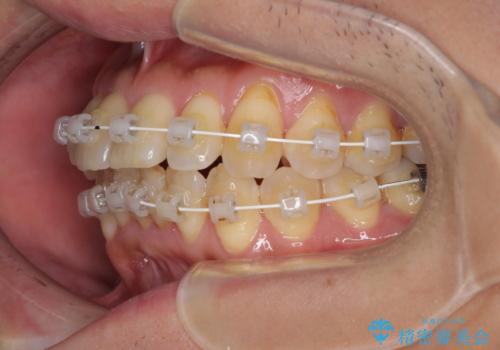

- 矯正装置

- 審美装置

治療開始の頃は、食事や歯磨きが慣れず、装置が頻繁に脱落しましたが、2,3ヶ月ほどで慣れ、その後は1年ほどで治療を終えることができました。